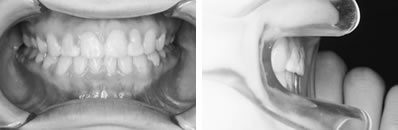

特別な装置を用いずに治療した例

パノラマレントゲンで前歯部分に過剰歯などの異常が無いことを確認。セファログラムレントゲンの分析から、左上の1番目の永久歯(中切歯)が内側に入っていることが問題であることを確認。

その後、木ヘラ(アイスの棒など)を用いて、歯を外側に出すトレーニングを行いました。